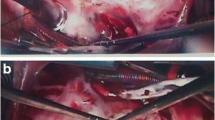

Displays end-diastolic tricuspid annuls (TA) measurements on 2D-TTE in the RV inflow long-axis view (a), short-axis view at the aortic valve level (b), apical four-chamber (c) and subcostal long-axis view (d). Image (e) display a multiplane area and image (f) details direct area measurement on the 3D